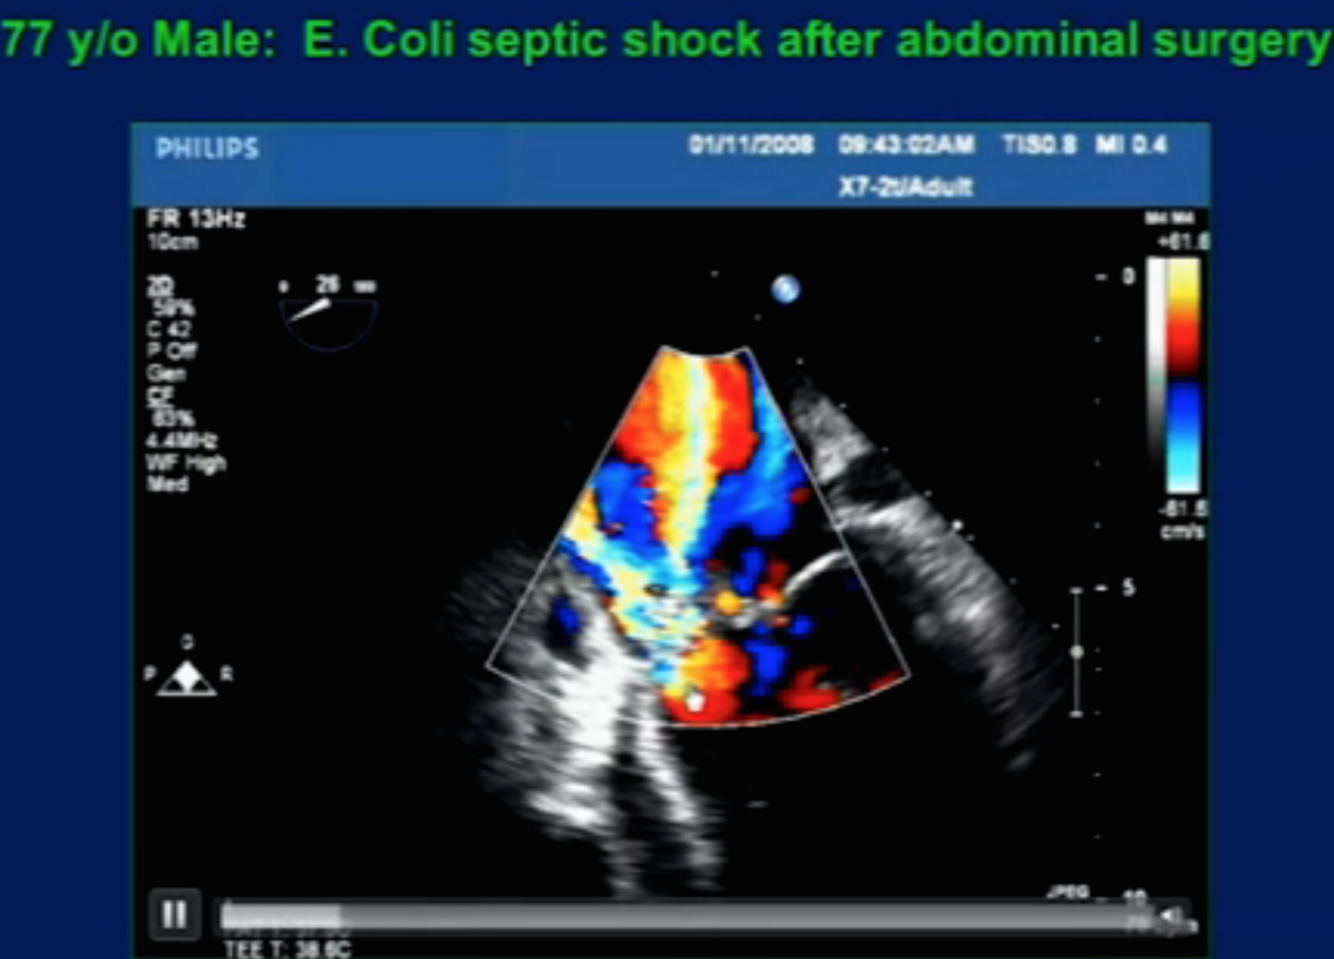

Diagnosis?

Perforated MV leaflet (*clue is to see the PISA off the midline)